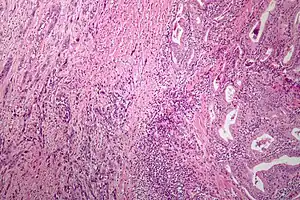

| Microscopic image of anaplastic thyroid carcinoma. H&E stain. | |

Anaplastic tumors have a high mitotic rate and frequently invades the local blood and lymphatic vessels.[5] Cellular death is frequently visualized on microscopic images.[2] The presence of regionally swollen lymph nodes in older patients in whom needle aspiration biopsy reveals characteristic vesicular appearance of the nuclei supports a diagnosis of anaplastic carcinoma. Microscopic images of ATC usually show inflammatory cells from the immune system such as T cells and macrophages.[2]

ATC is divided into several different subclasses based on its microscopic characteristics. These include sarcomatoid, squamoid, osteoclastic, paucicellular, rhabdoid, and carcinomasarcoid variants.[2] As of 2019, despite the fact that these ATC subtypes are recognized, this classification has not led to differences in management.[2] ATC is always considered to be stage IV when it is diagnosed.[6]